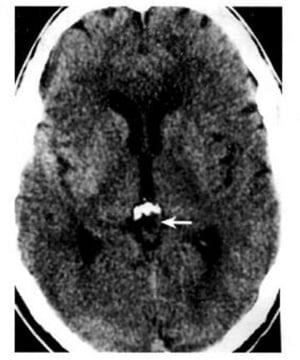

Hình 1.36. U tế bào mầm của tuyến tùng. Khối u bắt chất cản quang (mũi tên ngắn) nằm ở phía sau đóng vôi tuyến tùng bình thường (mũi tên dài).